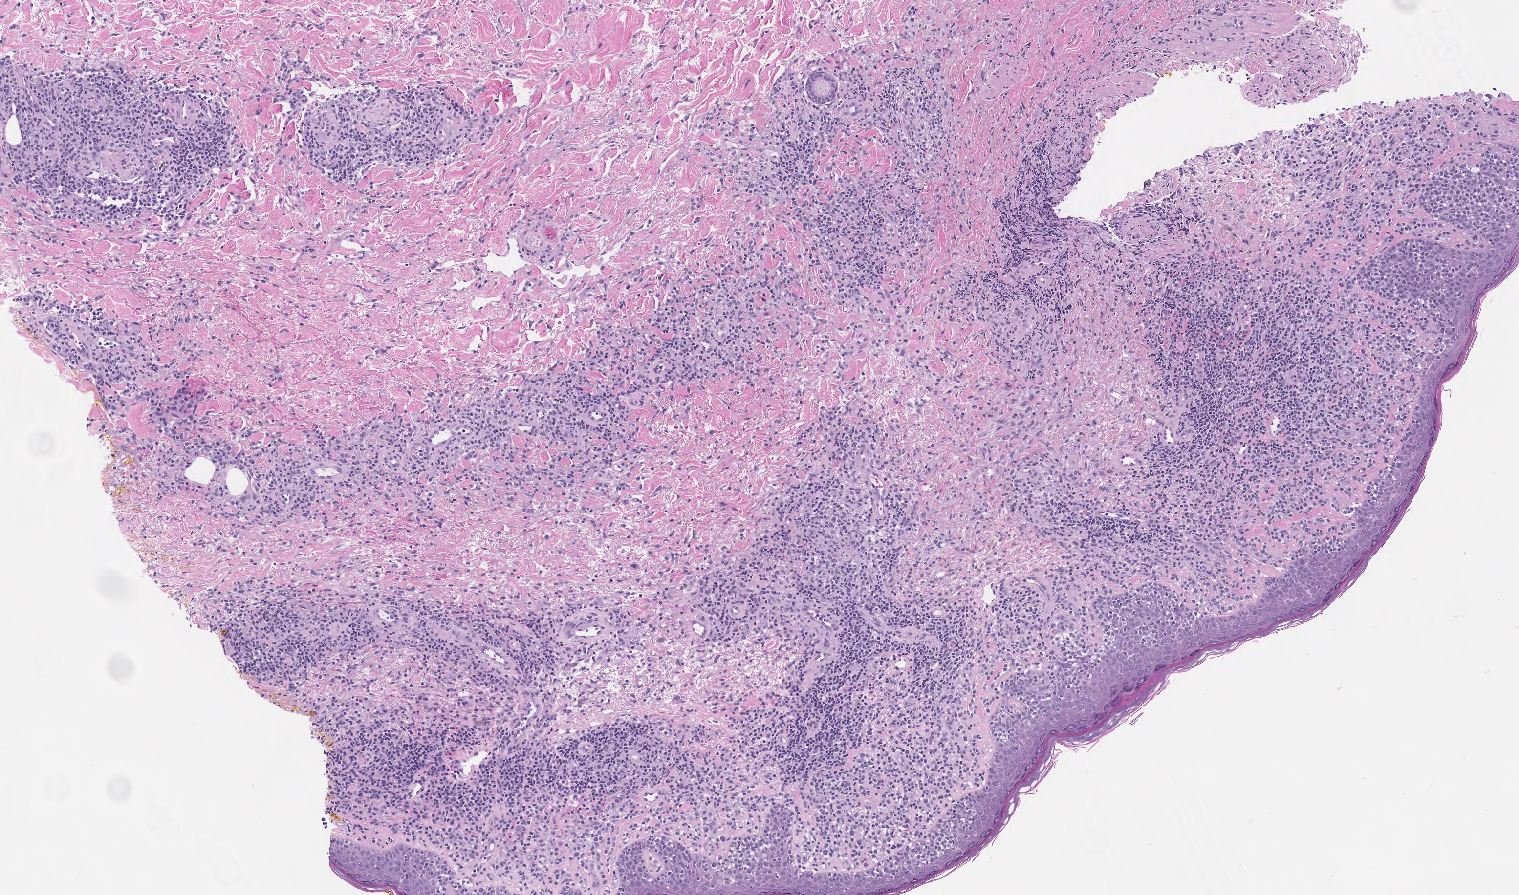

Case: Skin